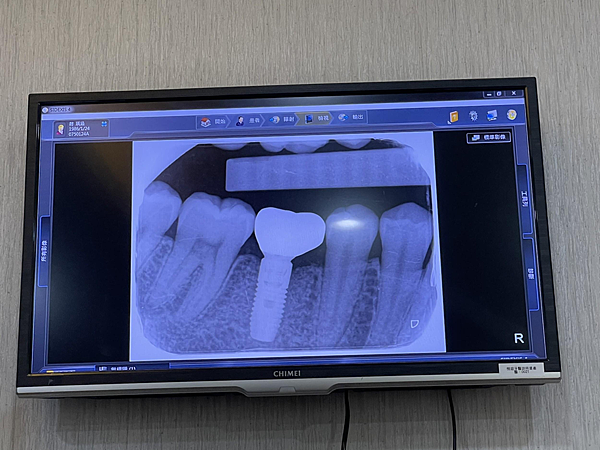

最后确认了我的骨头长的很好,高度宽度也够才放心的约下次正式植入植体的时间。

悦庭牙医使用的植体是有台湾卫生署认证的国际大厂植体,让我更放心的交给悦庭~

终于来到我植进植体的时间~真的超级兴奋~

整个过程大约1.5小时,医生专业的技术跟手术每次操作都会很清楚的解说,给人的感觉真的很安心,植牙的过程都是麻醉的所以不会痛,放心交给悦庭就对了!!

植完牙后,发了植牙的保证书给我,保固年限是10年。

ㄧ星期后回诊看植体稳定度跟牙肉状况,医生宣布很稳定时真的很开心~接下来就能等修复再放上假牙了